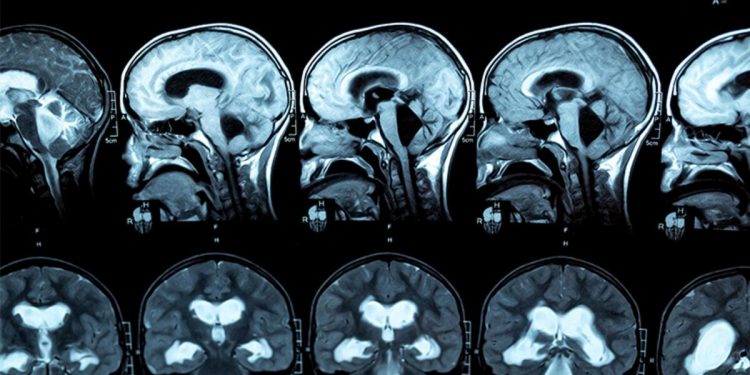

Halk ortasında ‘beyindeki su’ olarak bilinen hidrosefali, beyin omurilik sıvısının ventrikül olarak bilinen boşluklarda birikmesinden kaynaklanıyor. Hidrosefali kısaca, beyin omurilik sıvısının çoğalmasıyla, beyin karıncıklarının, kimi vakit da kafatasının büyümesine yol açan bir hastalık olarak tanımlanıyor. Beyin omurilik sıvısı, çok çeşitli beyin fonksiyonları için kritik bir ehemmiyete sahiptir.

Chloe’nin de durumu hayli ciddiydi. Fazla sıvı, beynin hafıza, karar verme ve histen sorumlu ön loblarını Chloe’nin kafatasının içine sıkıştırıyordu.

Chloe’ye MRI (Manyetik Rezonans Görüntüleme) taraması yapıldı. Bu tarama sonucunda ise Chloe’nin hidrosefalisinin, ventriküller ortasında tıkanmaya neden olan bir daralma olan akuaduktal stenozdan kaynaklandığını belirlendi.

Chu, Chloe’nin beynindeki basıncı azaltmak ve sıvının düzgün formda boşalmasını sağlamak için endoskopik üçüncü ventrikülostomi gerçekleştirdi.